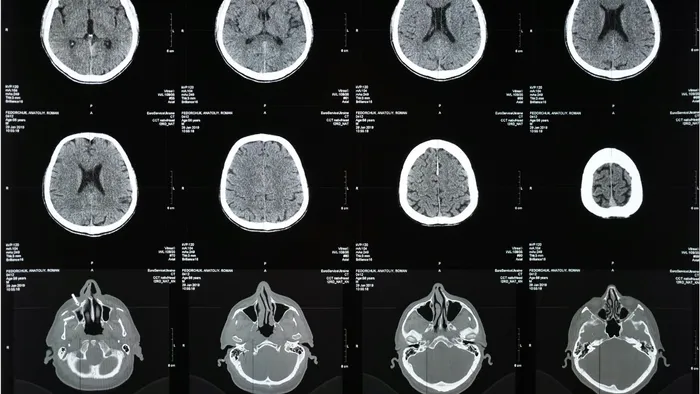

Beynin temel temizlik sisteminin, glimfatik sistem olarak adlandırılan ve beyin omurilik sıvısı aracılığıyla çalışan bir yapı olduğunu ifade eden Klinik Psikolog Zeynep Betül Alp, şöyle devam etti:

“Bu sistem, metabolik faaliyetler sonucu ortaya çıkan atık maddelerin beyinden uzaklaştırılmasını sağlar ve en aktif olduğu dönem derin uyku evreleridir. Özellikle öğrenme, hafıza ve nörodejeneratif hastalıklarla ilişkilendirilen proteinlerin temizlenmesi büyük ölçüde uyku sırasında gerçekleşir. Buna ek olarak kan-beyin bariyeri zararlı maddelerin beyne geçişini sınırlandırırken, mikroglial hücreler hücresel düzeyde temizlik ve onarım süreçlerinde rol alırlar. Dolayısıyla beynin ‘detoksu’, uyanıkken yapılan uygulamalardan ziyade, uyku ve fizyolojik denge ile ilişkilidir.”